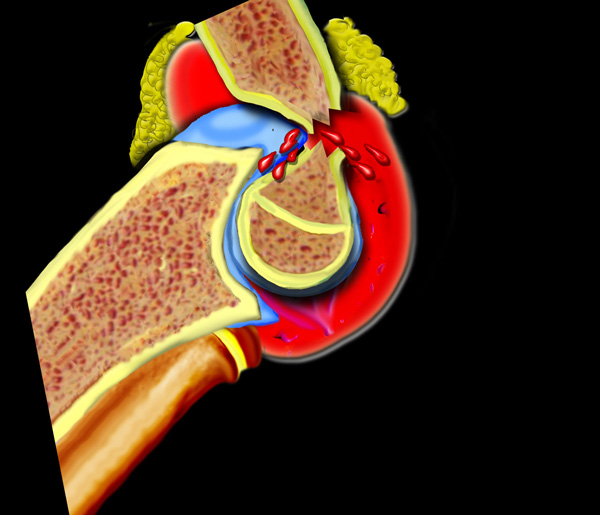

Thông thường trên phim chụp nghiêng của khớp khuỷu gấp 90°, có thể thấy một đệm mỡ ở phía trước của khớp.

Đây là lớp mỡ bình thường nằm trong bao khớp.

Ở phía sau không thấy đệm mỡ vì lớp mỡ phía sau nằm sâu trong hố gian lồi cầu.

Dấu hiệu đệm mỡ dương tính

Sự căng phồng của khớp sẽ khiến đệm mỡ phía trước bị nâng lên và đệm mỡ phía sau trở nên hiện rõ.

Vùng thấu quang phía trước bị nâng cao hoặc vùng thấu quang phía sau hiện rõ trên phim X-quang thẳng nghiêm thực sự của khuỷu tay gấp 90° được mô tả là dấu hiệu đệm mỡ dương tính (hình).

Tràn máu khớp gây ra sự dịch chuyển lên trên của đệm mỡ trước và sự dịch chuyển ra sau của đệm mỡ sau.

Bất kỳ sự giãn khớp khuỷu nào do xuất huyết, viêm hoặc chấn thương đều tạo ra dấu hiệu đệm mỡ dương tính.

Nếu không có dấu hiệu đệm mỡ dương tính ở trẻ em, tổn thương trong khớp đáng kể là khó xảy ra.

Dấu hiệu đệm mỡ có thể nhìn thấy mà không phát hiện được gãy xương nên được coi là gãy xương ẩn.